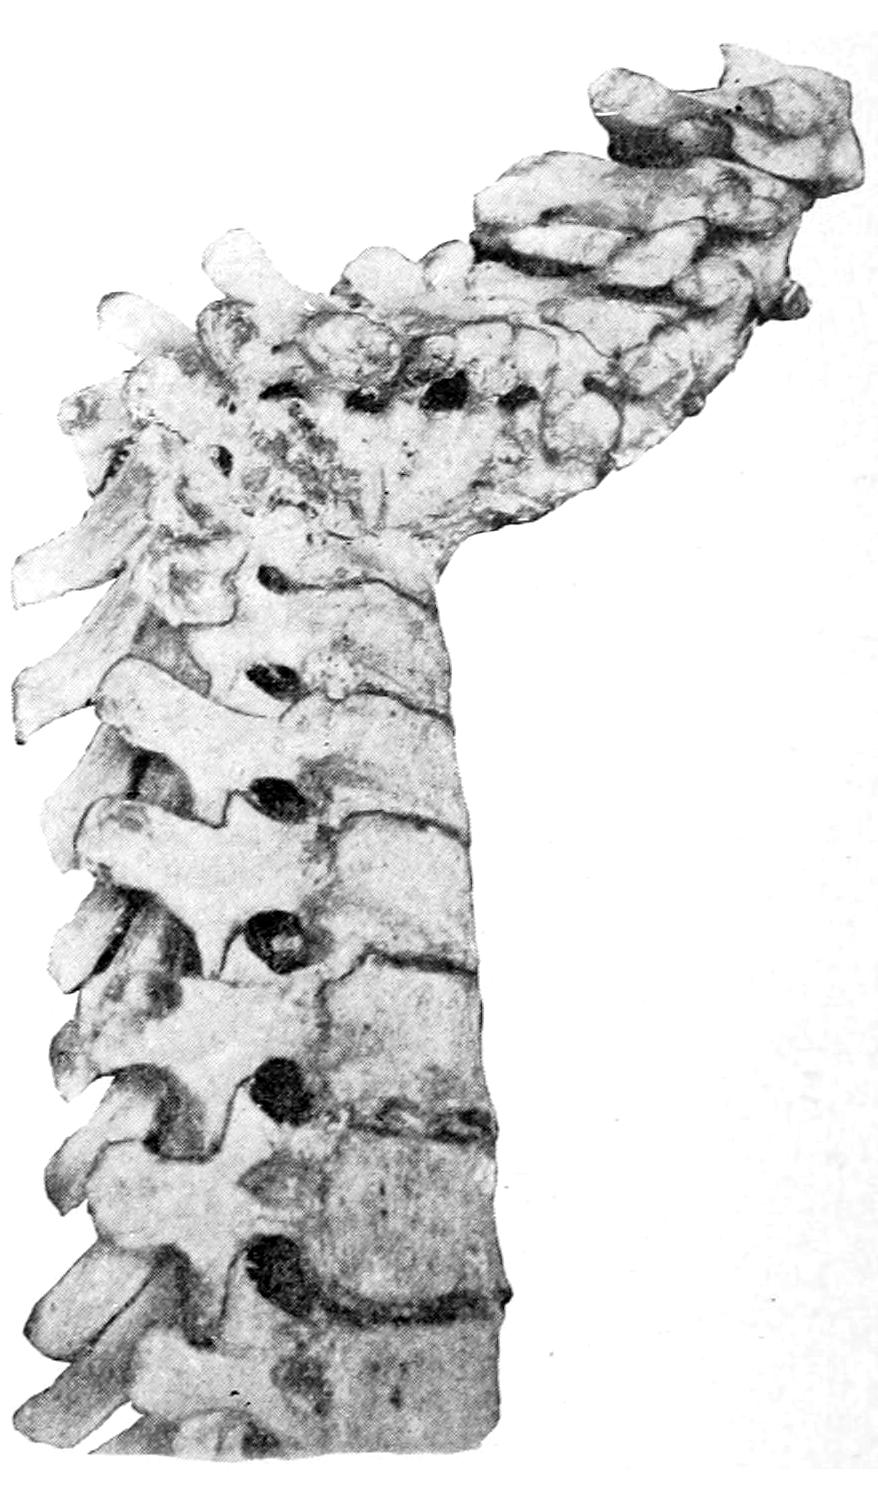

Within a few years a peculiar form of intense anemia has been described by Banti and others, and is often spoken of as splenic anemia or Banti’s disease. It is characterized by three stages: first, of splenic enlargement and anemia; second, a transitional stage; third, a stage of ascites which increases up to death. It is quite closely allied to Hanot’s hypertrophic cirrhosis of the liver. It is quite generally regarded as an example[32] of an infection by some as yet unknown organism. It is of interest to the surgeon because if the spleen is removed early there are fair prospects of recovery.